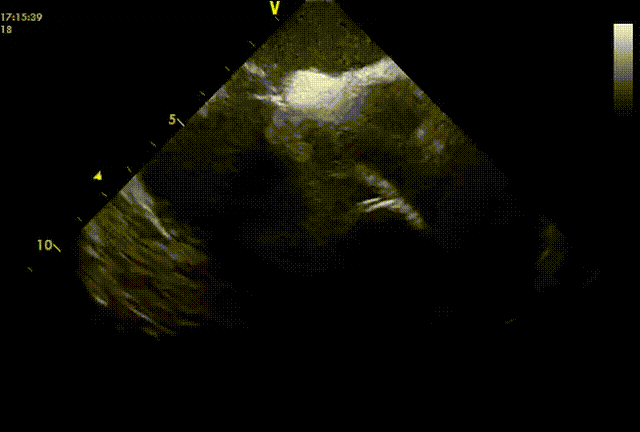

图片

封堵盘展开